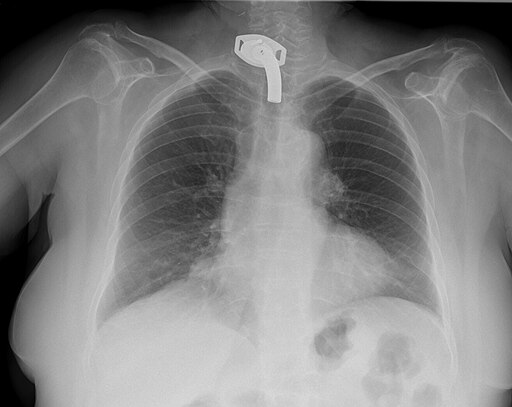

Jmarchn, CC BY-SA 3.0 https://creativecommons.org/licenses/by-sa/3.0, via Wikimedia Commons